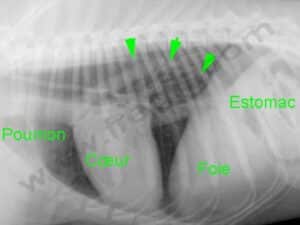

Radiographie du thorax d’un chien atteint d’un megaœsophage. Les flèches montrent le bord dorsal de l’œsophage dilaté.